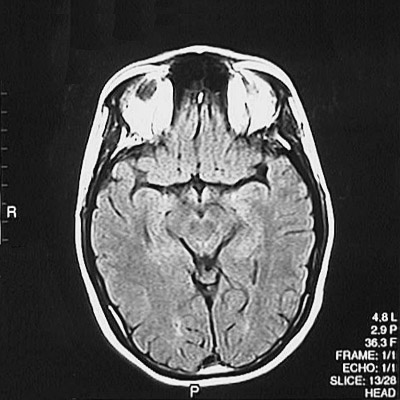

This is a normal axial FLAIR MRI scan demonstrating the inferior frontal lobe and temporal lobe and occipital lobe and cerebral peduncle and substantia nigra and red nucleus and aqueduct of Sylvius and frontal sinus and orbit.